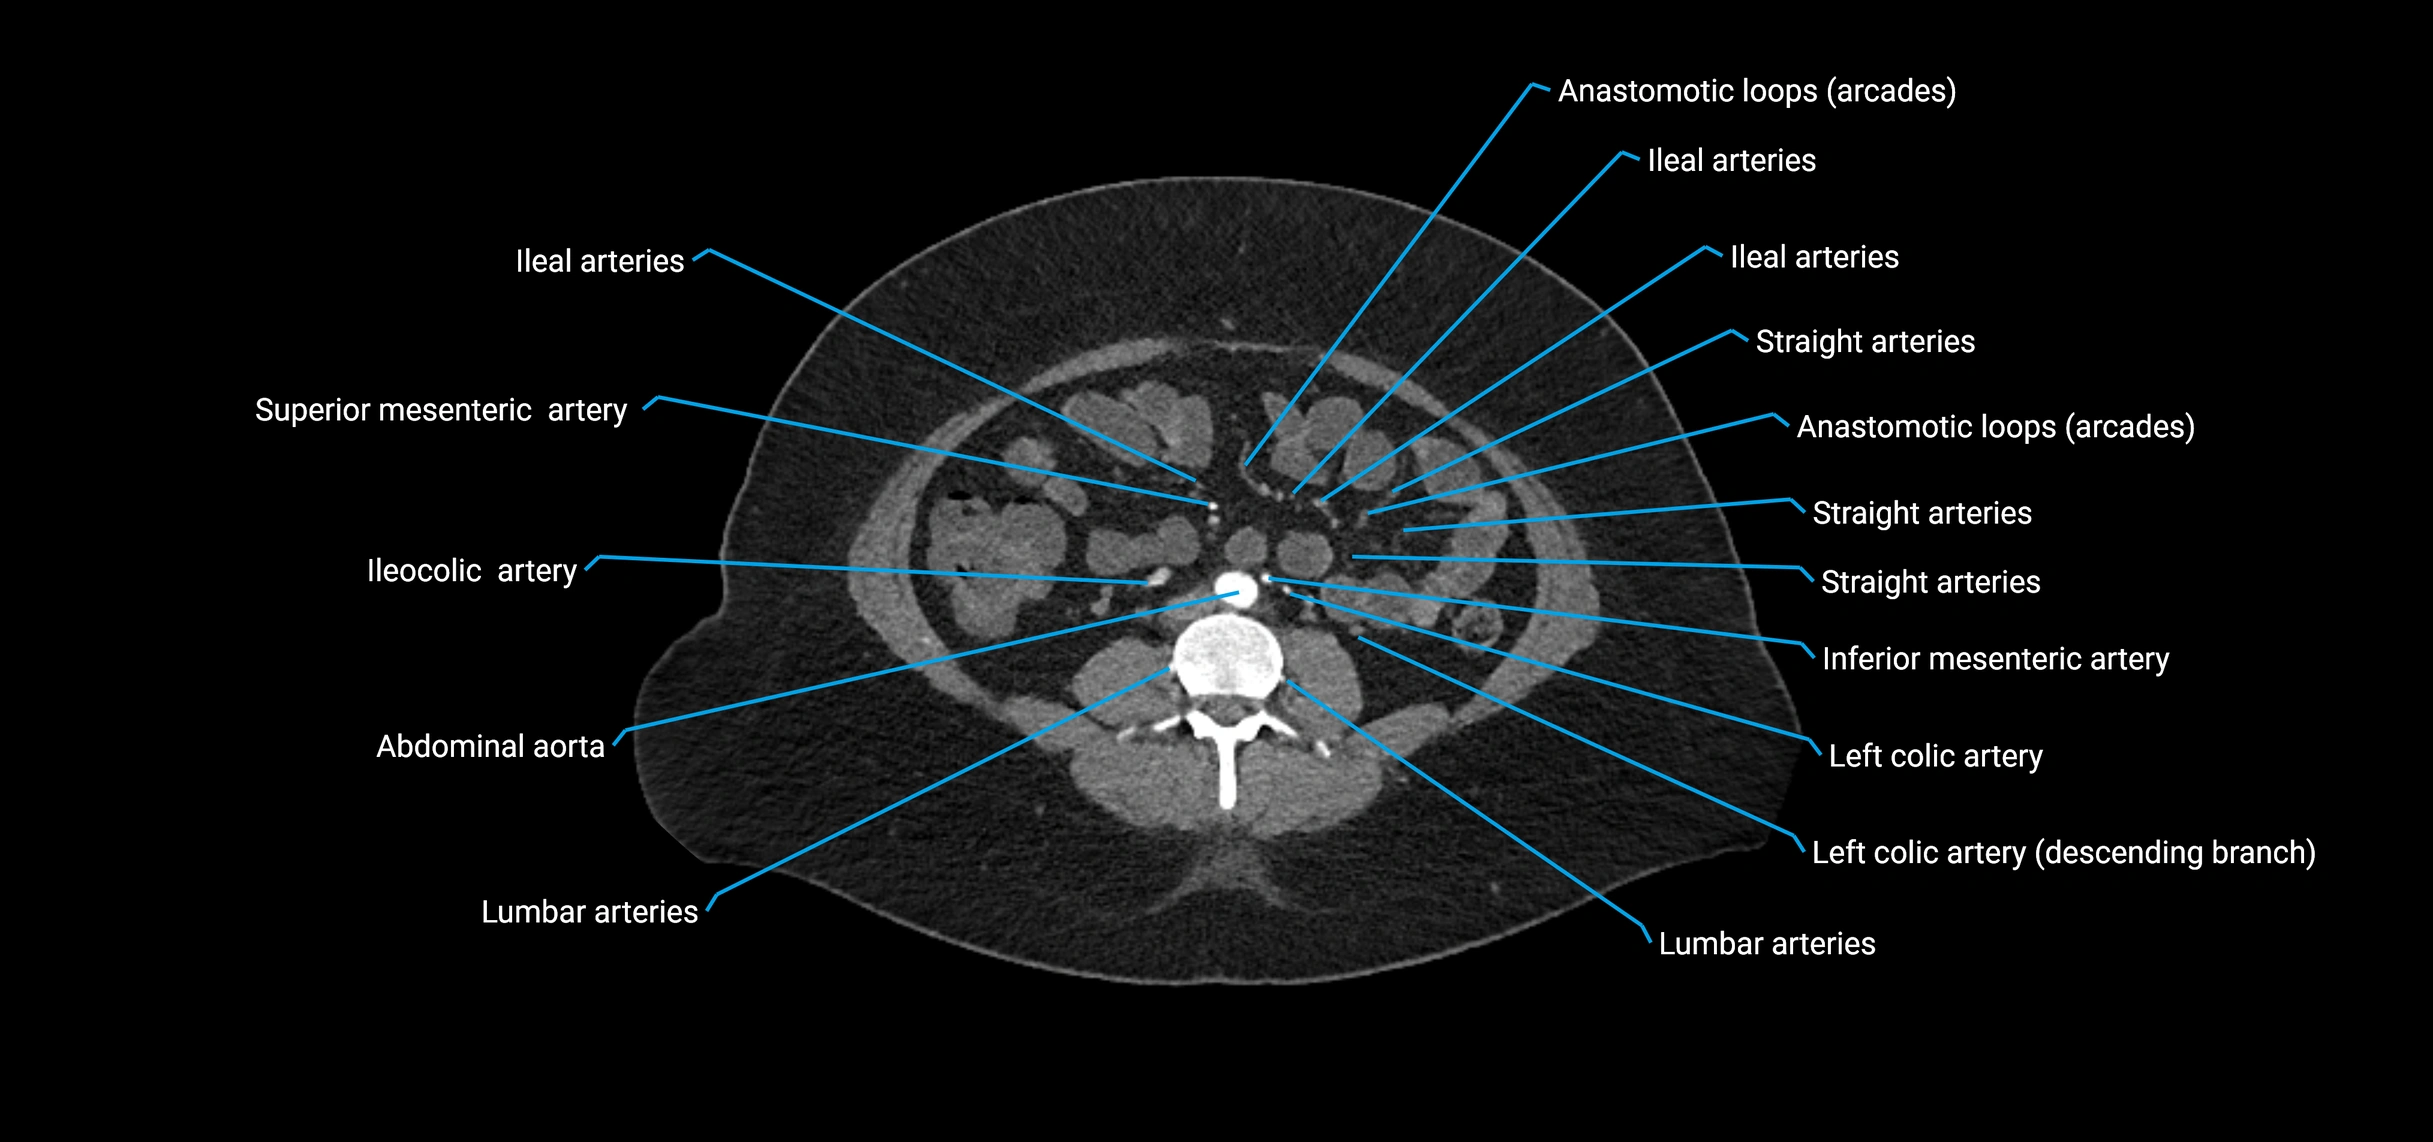

Contrast-enhanced CT (CTA):

• Gold standard for abdominal aortic imaging

• Provides excellent detail of lumen, wall, aneurysm, thrombus, and branch vessels

• Multiplanar and 3D reconstructions help in aneurysm measurement, stent graft planning, and dissection evaluation

• Unpaired visceral branches: celiac trunk, superior mesenteric artery (SMA), inferior mesenteric artery (IMA)

• Paired visceral branches: middle suprarenal arteries, renal arteries, gonadal arteries (testicular or ovarian)

• Parietal branches: inferior phrenic arteries, lumbar arteries, median sacral artery

• Terminal branches: right and left common iliac arteries